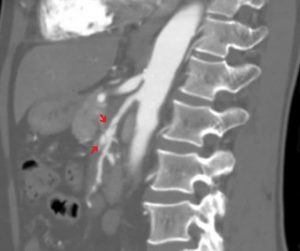

Median arcuate ligament syndrome

Patients with chronic post-prandial epigastric pain may have median arcuate ligament syndrome (MALS). The median arcuate ligament is a part of the diaphragm that surrounds the aorta. The diaphragm moves with respiration. In theory, this movement may cause tension on the celiac artery or on the nerves surrounding the celiac plexus. But there is much…